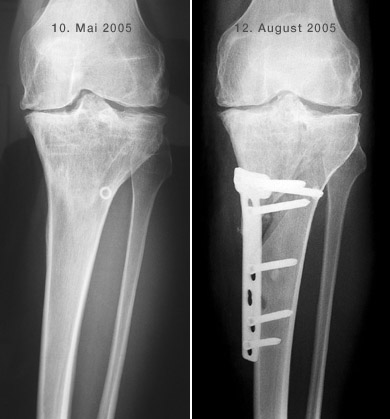

Hier ist schön sichtbar, wie die Gelenksachse korrigiert wurde